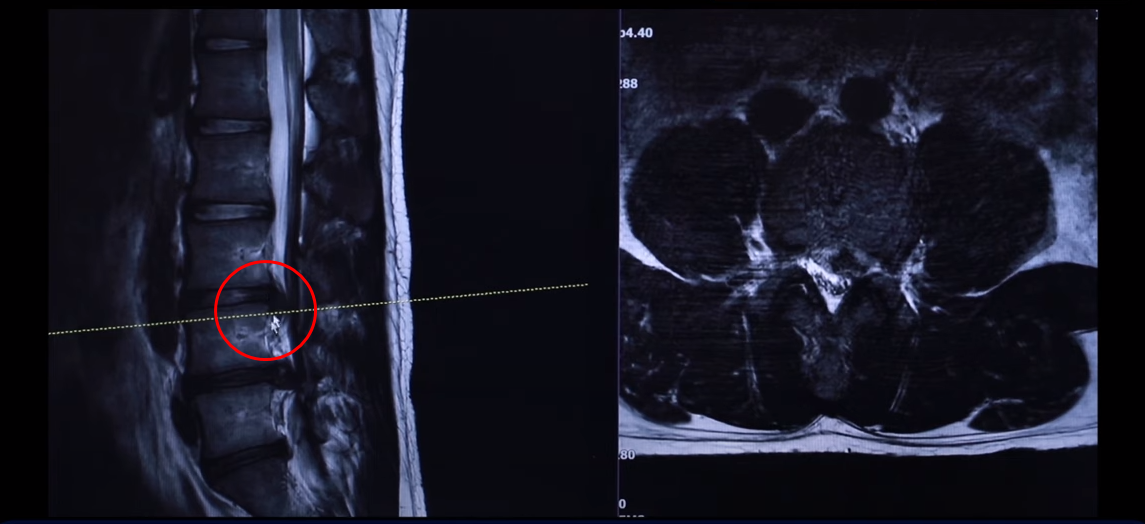

여기 24세 남자 환자분 MRI 보도록 하겠습니다. 옆에서 보는 MRI 보시다시피 어마어마하게 지금 심하게 터져 있습니다. 일반인이 보셔도 아실 정도로 두 마디가 아주 심하게 터졌고 여기도 약간 밀려 나와 있습니다.

단면을 한번 보도록 하겠습니다. 여기를 잘라서 본 단면인데요. 왼쪽으로 많이 밀려 나와 있죠? 이 한마디만 해도 파열돼서 상당히 많이 밀려 나온 겁니다. 왼쪽 다리가 저리고 아플 수 있습니다.

그 다음 마디 4번, 5번 보시면 보시다시피 아예 신경이 거의 보이지 않을 정도로 많이 밀려나왔습니다. 이렇게 심하게 파열된 경우를 보는 건 참 드뭅니다. 거의 신경이 보이지 않을 정도로, 오른쪽에 약간 하얀 부분이 남아 있습니다. 그래서 이 환자분 증상이 왼쪽 다리 증상입니다.